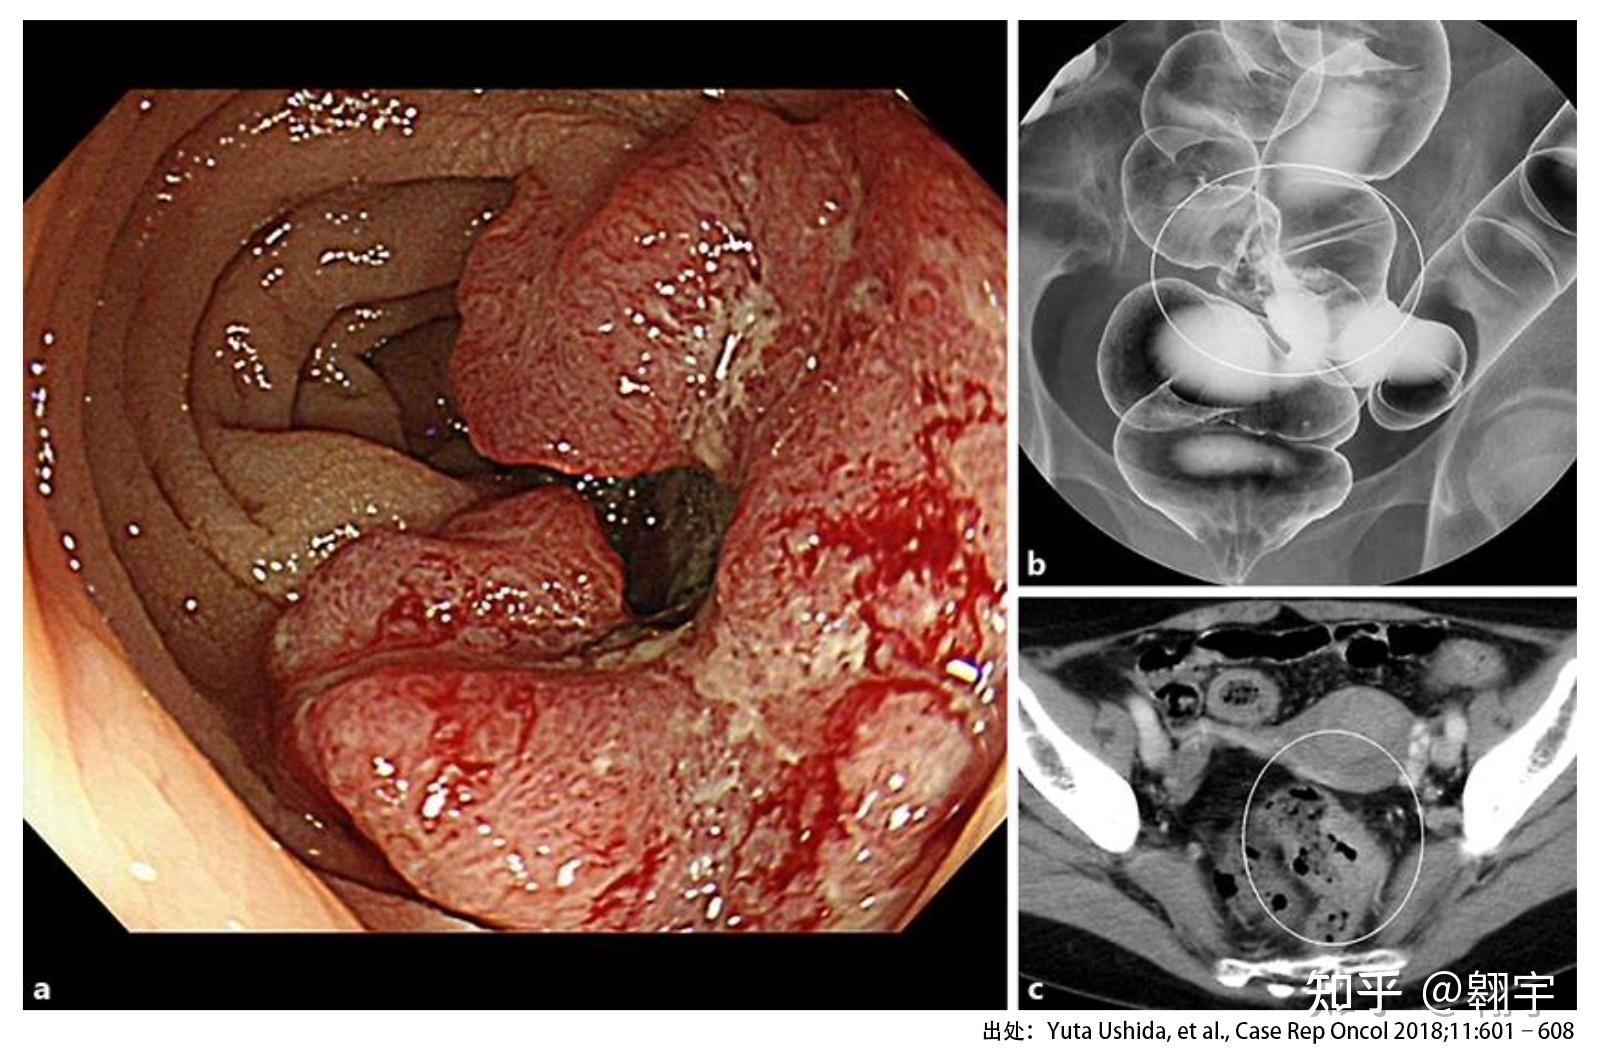

盲肠癌1例

图片尺寸680x579

于阑尾炎手术创面呈浸润性发育的盲肠癌 posted by: oita pref.